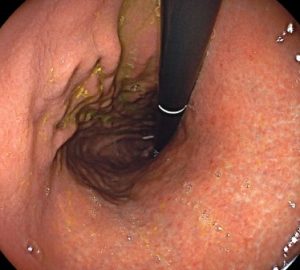

La gastritis es la inflamación del revestimiento del estómago. Puede ser aguda, que es de corta duración, o crónica, cuando persiste durante un período prolongado. La causa más común de gastritis es una infección bacteriana por Helicobacter pylori, aunque también puede ser causada por el uso excesivo de medicamentos antiinflamatorios no esteroideos (AINEs), consumo excesivo de alcohol, estrés, fumar, trastornos autoinmunes u otras enfermedades.